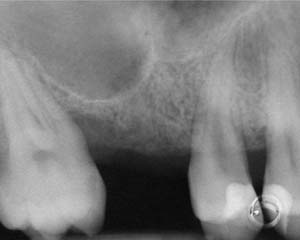

A 55-year-old male was referred for implant placement and prosthetic rehabilitation in the area of tooth No. 15. The tooth had been extracted 4 years prior. The radiograph revealed inadequate bone height for implant positioning (Figure 6). It was decided to insert an implant that was 11.5 mm in length and 3.75 mm in diameter, performing a slight osteotomic maxillary sinus lift. A heterologous bone graft also was planned to obtain a larger sinus lift.

Figure 6 Preoperative radiograph of the area around tooth No. 15.